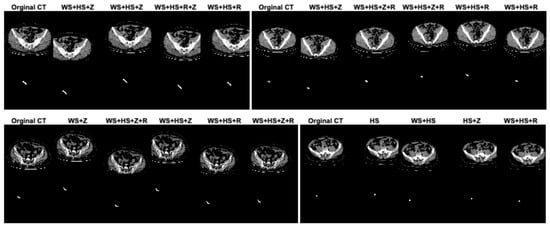

In this study, data augmentation was performed to address several key challenges in training deep learning models for appendix segmentation in CT scans. Data augmentation was applied to artificially increase the size and variability of the prepared dataset. This helps to avoid overfitting [], where the model memorizes the training data rather than learning generalizable features. In addition, the CT scans in the dataset can vary significantly between patients in terms of anatomical differences, scan quality, patient position and image noise. The data augmentation enables the proposed U-Net deep learning architecture to learn more robust and discriminative features. This improves the model’s ability to generalize to unseen data by simulating variations in real CT scans. In this study, in the original dataset prepared for appendix segmentation, the number of slices in the training set was increased from 1199 to 2399, the number of CT slices in the test set was increased from 221 to 441, and the total number of slices was increased from 1420 to 2840 using data augmentation strategies. The data augmentation procedures used to increase the size of the dataset were width_shift_range = 0.2 (WS), height_shift_range = 0.2 (HS), rotation_range = 2 (R) and zoom_range = 0.05 (Z). The data augmentation procedures for the dataset were randomly generated on both training and test sets separately or together. Figure 4 shows the effect of the data augmentation procedures on some CT scans and GT masks in the dataset.

Figure 4.

The effect of the data augmentation procedures on some CT scans and GT masks in the dataset.